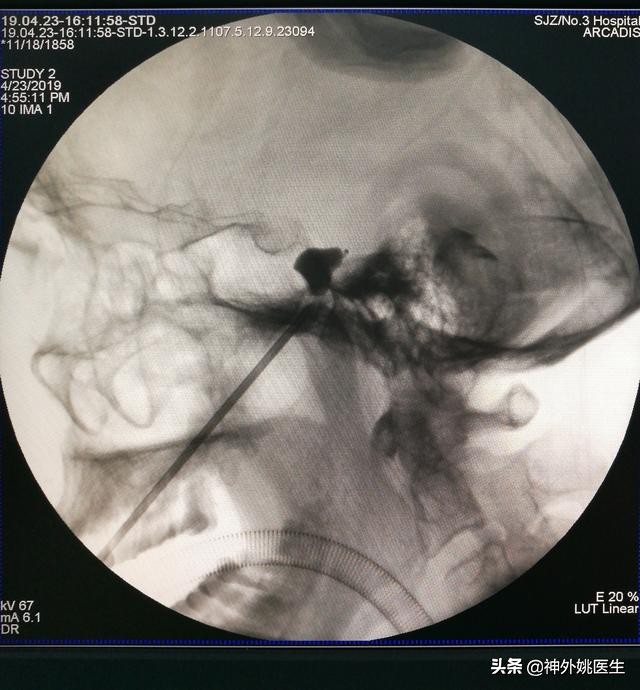

3、C型臂定位引导下穿刺颅底卵圆孔,调整穿刺针,使其进入Meckel`s囊。(图5)。

图5